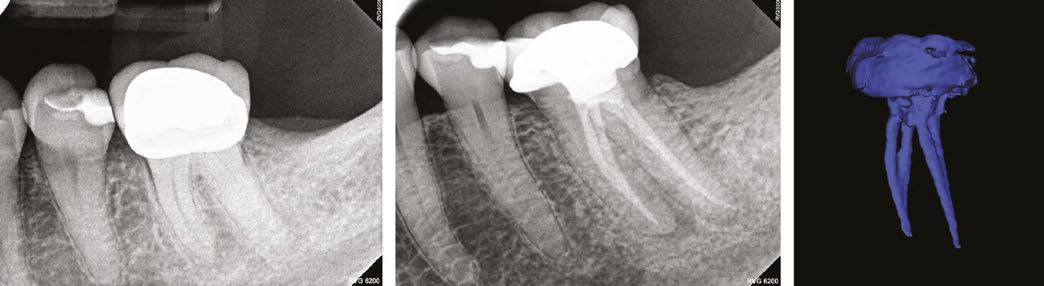

Case 1

A 43-year-old female patient with a noncontributory medical history was referred with a chief complaint of a bad toothache that was very painful to touch. The patient reported a history of trauma and had been told that tooth No. 8 had been dead for years. There was a history of internal bleaching 4 years prior with some success, but the shade had regressed. Clinical examination of the right first maxillary central revealed fluctuant swelling of

the labial gingiva. Radiographic examination revealed a lingual composite restoration and a blunted root tip with calcific metamorphosis. Also, a periapical lesion was associated with the root canal (Figure 1A). The patient’s history of symptoms and the clinical examination indicated a pulpal diagnosis of pulp necrosis and an acute apical abscess. After a review of options with the patient, root canal treatment with internal bleaching was recommended to retain the tooth, and the patient consented to care.

A standard anesthesia protocol (lidocaine with 1:100.000 epinephrine and articaine with 1:200.000 epinephrine through buccal and palatal infiltration) was followed, and the tooth was isolated with a rubber dam. A dental operating microscope was utilized for creating a minimally invasive, straight-line endodontic access opening. After patency and working length were established, mechanical instrumentation was prepared with No. 20 variable taper SlimShaper® file (Avalon Biomed, Houston, Texas). Following minimal preparation, debridement and disinfection were completed utilizing the GWS, where sodium hypochlorite (NaOCI) + distilled water + ethylenediaminetetraacetic acid (EDTA) + distilled water were delivered using Multisonic UItracleaning technology (Figure 1B). After the cleaning process, the root canal was dried using sterile paper points. A single cone technique employing gutta percha and bioceramic sealer (EndoSequence® BC Sealer HiFlow; Brasseler USA, Savannah, Georgia) was utilized during obturation. A coronal seal was placed, and the access cavity was sealed with temporary filling material. The patient was advised to return to the referring general dentist for internal bleaching.

tissue lesions, or root resorption radiographically. After 2 years of GWS, cone beam computed tomography (CBCT) images show intact lamina dura and growth of trabecular bone in Figure 1D.

Case 2

A postoperative radiograph is presented in Figure 1C. At the 2-year recall, the patient was asymptomatic. Upon clinical and radiographic examination, there was no painful response to percussion or palpation, no presence of mobility, fractures, soft

A 75-year-old female patient with a noncontributory medical history was referred with a chief complaint of dull pain in the lower right quadrant for 1 month, worsened by pressing on the gum. The patient reported a history of crown preparations of teeth Nos. 30 and 31, 1 week prior. Gingival swelling for several days had partially subsided since starting antibiotic therapy. Clinical examination of the right first maxillary molar (No. 30) revealed negative sensitivity to percussion and a mild pain response to palpation. There was a vestibular swelling over the mesial root of tooth No. 30. Vitality testing elicited a negative response. Radiographic examination revealed a large periapical lesion on the mesial root of tooth No. 30 (Figure 2A). The patient’s history of symptoms and the clinical examination indicated a diagnosis of

Figure 1A (left): Preoperative image of Case 1. Figure 1B (middle): Image of GentleWave. Figure 1C (right): Post-GentleWave procedure radiograph of Case 1

Figure 1D: 2-years post-GentleWave procedure recall with healing periapical lesion of Case 1

pulp necrosis and an acute apical abscess. After a review of options with the patient, endodontic therapy was recommended to retain the tooth.

After standard local anesthesia and isolation protocols, the temporary crown was removed, and the tooth was accessed under the dental operating microscope. Upon entry to the pulp chamber, necrotic tissue and purulence was noted from the mesial canals. After patency and working length were established, mechanical instrumentation was prepared with at No. 20 variable taper SlimShaper file. Following minimal preparation, debridement and disinfection were completed utilizing the GWS, where sodium hypochlorite (NaOCI) + distilled water + ethylenediaminetetraacetic acid (EDTA) + distilled water were delivered using Multisonic UItracleaning technology. After the cleaning process, root canals were dried using sterile paper points. A single cone technique employing gutta percha and bioceramic sealer were utilized during obturation (Figure 2B). A coronal seal was placed, and the temporary crown was re-cemented with TempBond™ (Kerr).

Upon completion of endodontic therapy with the GWS, at the 6-month recall, the tooth was asymptomatic (Figure 2C). The CBCT was taken, and images showed complete healing of the apical bone (Figure 2D).

Figure 2B: Post-GentleWave procedure obturated root canal system of Case 2 Figure 2C: 6-month recall postoperative radiograph of Case 2

Figure 2D: CBCT images with no evidence of periapical lesion of Case 2